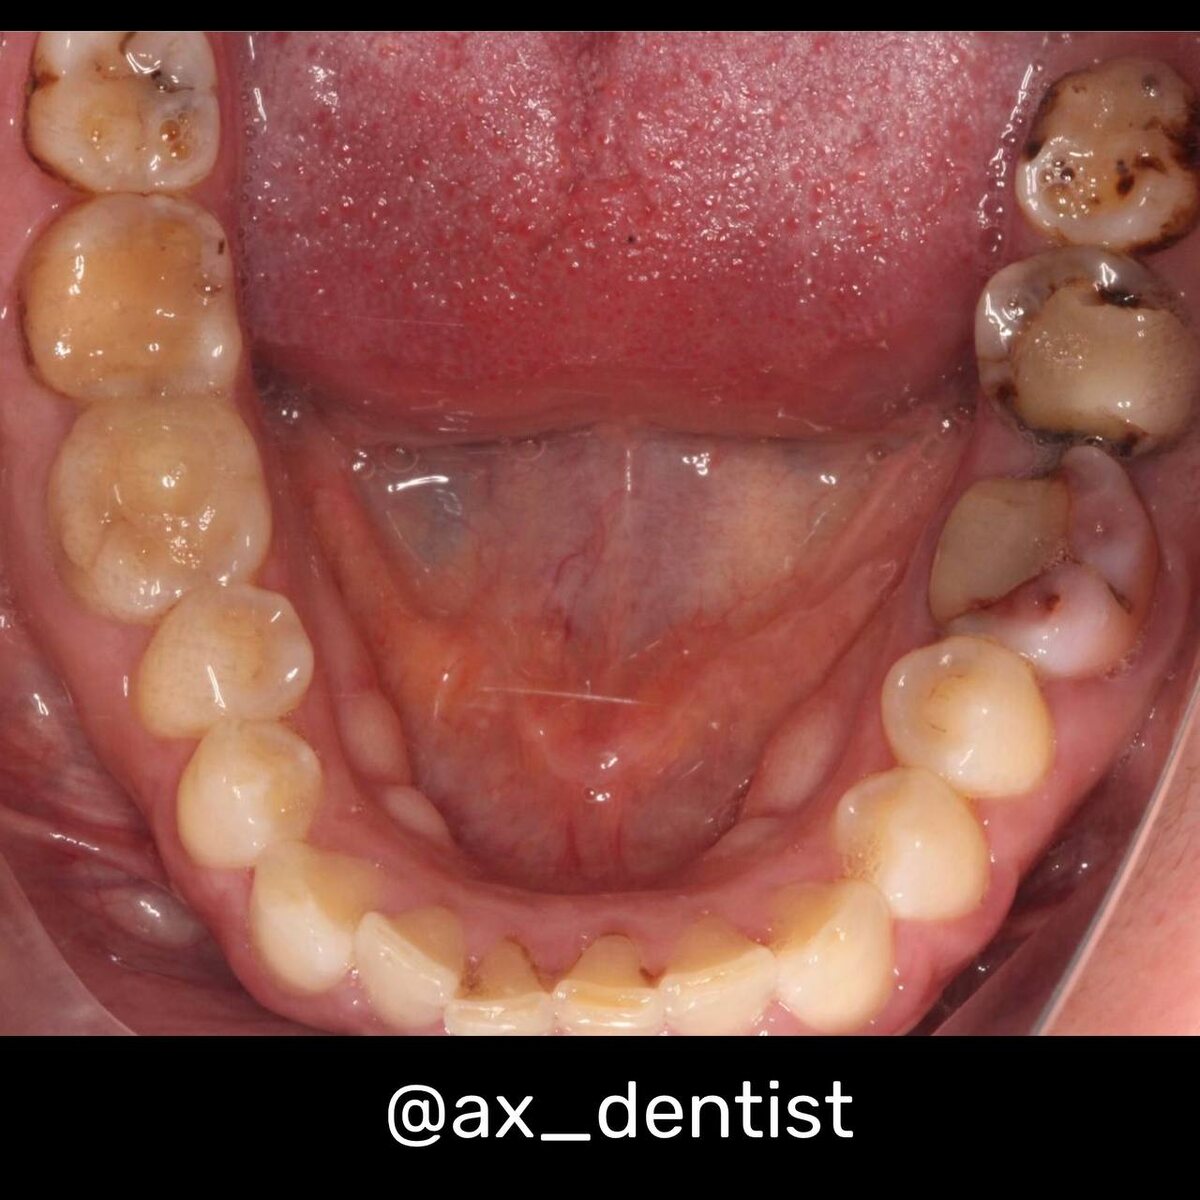

Нижний шестой зуб окрашен резорцион-формалином

Если вам лечили зуб 20-30 лет назад, есть шанс, что каналы пломбировали пастой на основе резорцина и формалина. Она была долговечной, но имела побочный эффект: со временем она намертво окрашивала дентин в ядовито-розовый или густой коричневый цвет. Такой зуб не просто темный. Он выглядит «мертвым» и не поддается никаким внешним методам осветления. Это боль пациента, который годами живет с «пятном» в улыбке, хотя сам зуб давно вылечен. Это эстетическая несправедливость, которую можно устранить только изнутри.